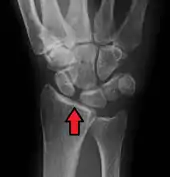

Scapholunate ligament disruption associated with a Colles' fracture